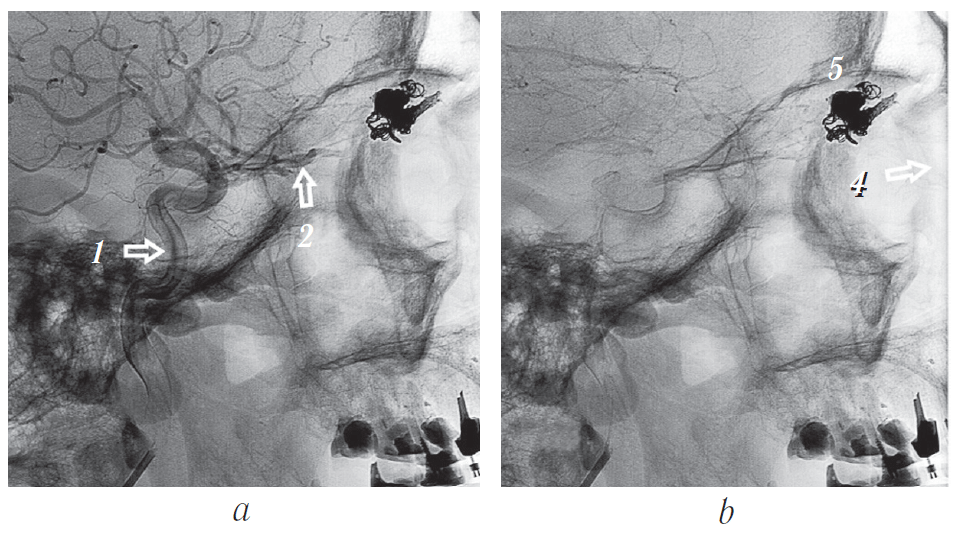

Катетеризирована правая внутренняя сонная артерия. Выполнена стандартная и ротационная ангиография. При стандартной субтракционной (рис. 13) и ротационной (рис. 14) ангиографии визуализируется выраженная собственная сосудистая сеть новообразования правой орбиты, источником которой является правая глазная артерия. Венозный отток осуществляется по варикозно расширенной дренирующей угловой вене, впадающей в лицевую вену.

Рис. 14. Ротационная ангиограмма: a — общий вид в боковой проекции; b — вид сосудистой сети новообразования слева; c — вид сосудистой сети новообразования справа. 1 — глазная артерия; 2 — центральная артерия сетчатки; 3 — собственно сосудистая сеть новообразования; 4 — дренирующая вена; 5 — афференты сосудистой сети; 6 — варикозно расширенное устье дренирующей вены; 7 — артериовенозные фистулы (шунты)

Fig. 14. Rotational angiogram: a – general appearance in lateral view; b – left-side appearance of vascular network of the tumor; c – right-side appearance of vascular network of the tumor. 1 – ophthalmic artery, 2 – central retinal artery, 3 – proper vascular network of the neoplasm, 4 – draining vein, 5 – vascular network afferents, 6 – varicose dilated drainage vein opening, 7 – arteriovenous fistulas (shunts)